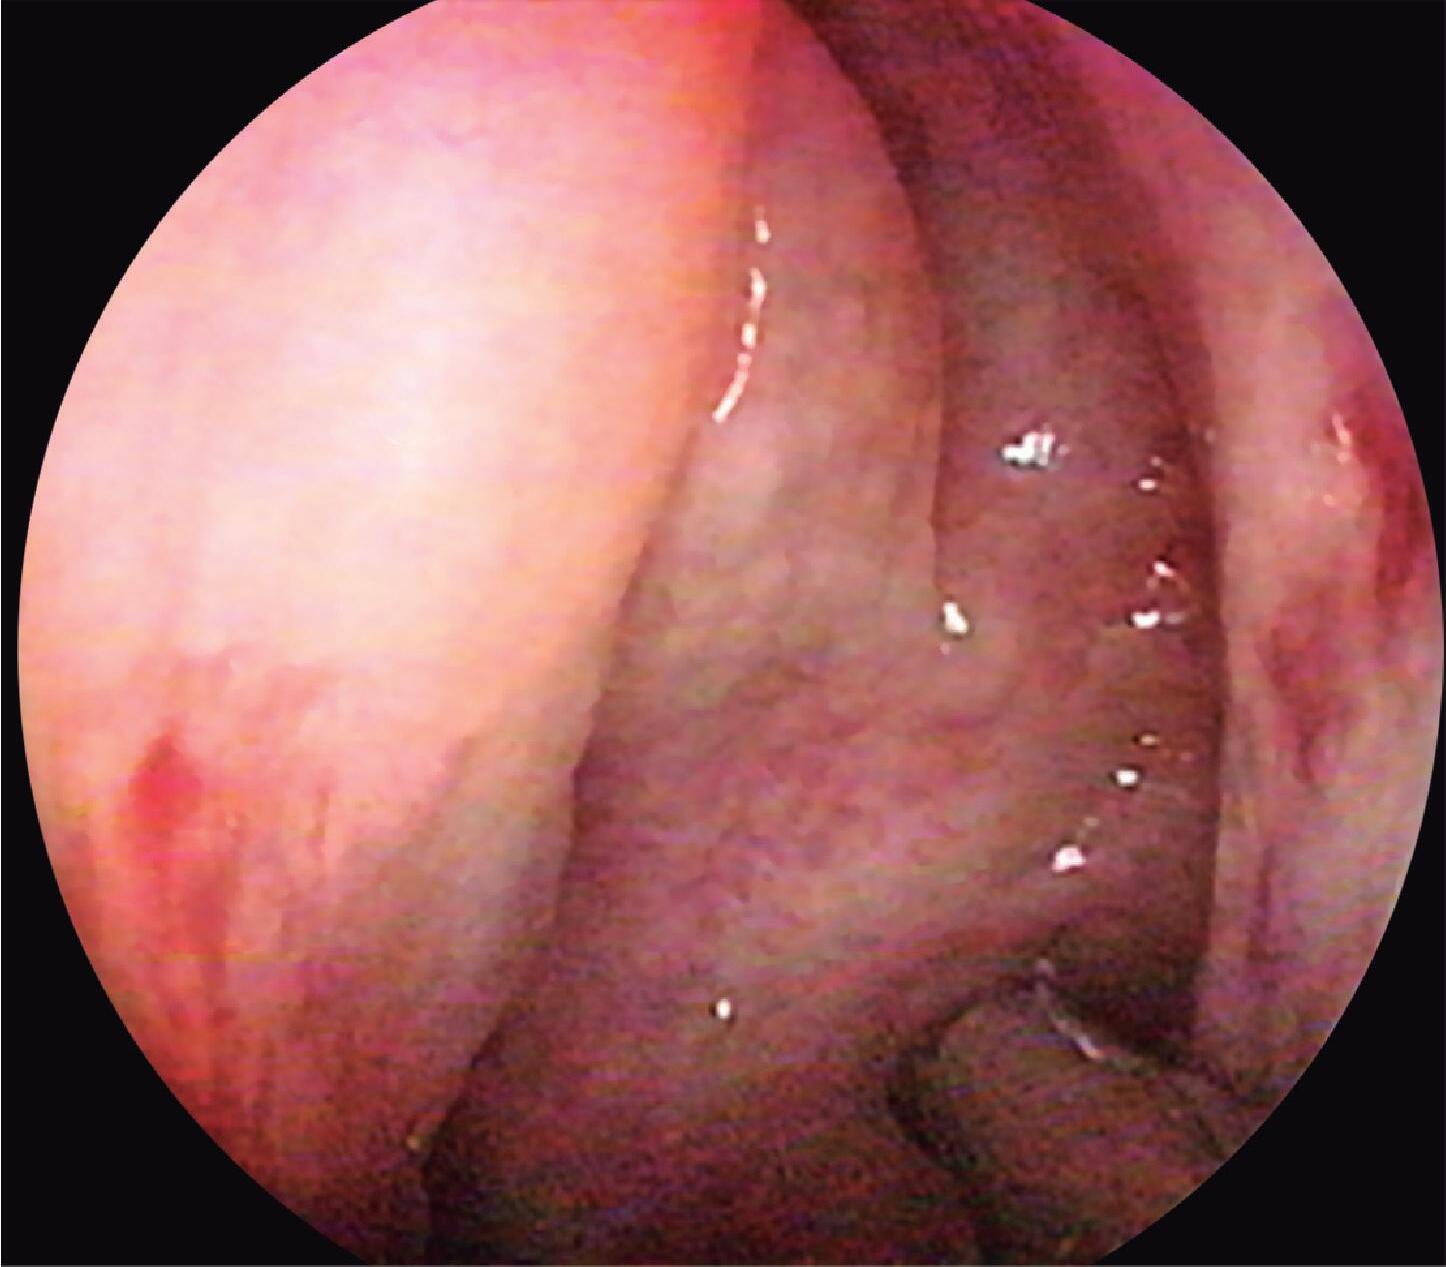

Fig. 1-24. Visão endoscópica do óstio esfenoidal direito – observar posição medial à concha superior; (1) septo, (2) óstio esfenoidal, (3) concha superior, (4) meato superior.